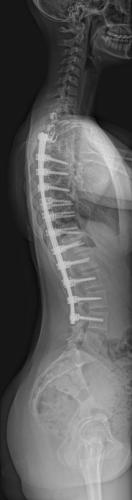

Images de scolioses opérées 16 janvier 202418 janvier 2023 par Damien Scoliose thoraco-lombaire 1 Radio préopératoire de Face Radio préopératoire de Profil Radio de Face à 2 ans de recul Radio de Profil à 2 ans de recul